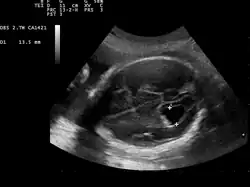

Prenatal ultrasound showing a well defined hypoechoic lesion corresponding to a choroid plexus cyst